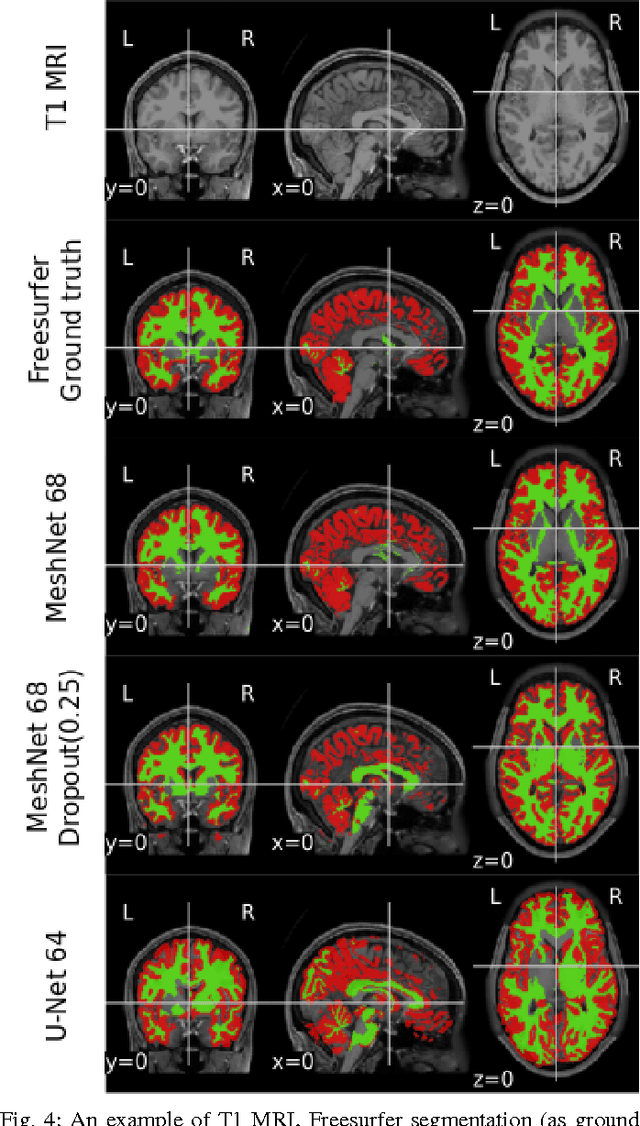

Segmenting a structural magnetic resonance imaging (MRI) scan is an important pre-processing step for analytic procedures and subsequent inferences about longitudinal tissue changes. Manual segmentation defines the current gold standard in quality but is prohibitively expensive. Automatic approaches are computationally intensive, incredibly slow at scale, and error prone due to usually involving many potentially faulty intermediate steps. In order to streamline the segmentation, we introduce a deep learning model that is based on volumetric dilated convolutions, subsequently reducing both processing time and errors. Compared to its competitors, the model has a reduced set of parameters and thus is easier to train and much faster to execute. The contrast in performance between the dilated network and its competitors becomes obvious when both are tested on a large dataset of unprocessed human brain volumes. The dilated network consistently outperforms not only another state-of-the-art deep learning approach, the up convolutional network, but also the ground truth on which it was trained. Not only can the incredible speed of our model make large scale analyses much easier but we also believe it has great potential in a clinical setting where, with little to no substantial delay, a patient and provider can go over test results.